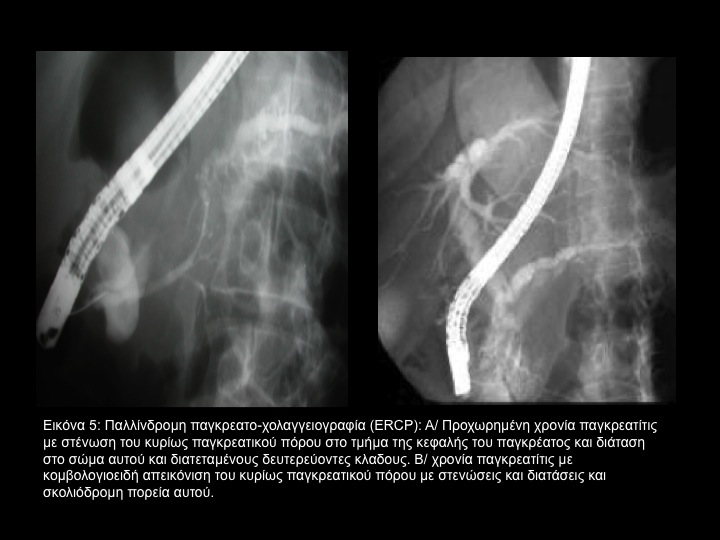

Πρώϊμες αλλαγές παρατηρούνται στους πλευρικούς κλάδους του κυρίως παγκρεατικού πόρου, που περιλαμβάνει διάταση με καθοδική στένωση, ενδαυλική ανωμαλία του βλεννογόνου και ενδαυλικό έλλειμμα πληρώσεως λόγω πρωτεϊνούχων καθιζημάτων ή λίθων. (Εικόνα 4) Ο αριθμός των αδιαφανών πλευρικών κλάδων μπορεί να είναι μειωμένος κατά τρόπο εστιακό ή διάχυτο, λόγω αποφράξεως του πόρου.

Σε όψιμα στάδια της νόσου, προέχουσες είναι οι αλλαγές στον κύριο παγκρεατικό πόρο και είναι παρόμοιες με εκείνες των πλευρικών κλάδων του παγκρεατικού πόρου, όπως ενδοπορική διάταση με ή χωρίς στένωση, βραχείες τμηματικές στενώσεις ή μακρές στενώσεις και ενδαυλικά ελλείμματα πληρώσεως οφειλόμενα σε πρωτεϊνικές καθιζήσεις ή λίθους.

Ο παγκρεατικός πόρος μπορεί να δείξει κομβολογιοειδή απεικόνιση ή αλυσίδα λιμνών λόγω εναλλασσόμενων στενώσεων και διευρύνσεων του παγκρεατικού πόρου. Μικρές (1-2 cm) στρογγύλες ή ωοειδείς, ανώμαλες ή καλώς αφοριζόμενες παρεγχυματικές παγκρεατικές κοιλότητες μπορεί να παρατηρηθούν. (Εικόνα 5) Αλλαγές στο κοινό χοληδόχο πόρο είναι συχνές στη χρονία παγκρεατίτιδα. Το συνηθέστερο εύρημα είναι μακρά λεία στένωση του πόρου με βαθμιαία οξύαιχμο απόληξη του περιφερικού τμήματος λόγω περιπορικής ινώσεως. (Εικόνα 6) Σε 25% των ασθενών με χρονία παγκρεατίτιδα,  η εναλλαγή στενώσεων και διατάσεων του κοινού χοληδόχου πόρου μπορεί να του προσδώσει κλεψυδροειδή απεικόνιση.

Η ERCP είναι η περισσότερο ευαίσθητη και ειδική τεχνική για τη χρονία παγκρεατίτιδα, αν και είναι επεμβατική και μπορεί να προκαλέσει επεισόδια οξείας παγκρεατίτιδος και ανιούσης χολαγγεϊτιδος.

Αν και τα ευρήματα της ERCP μπορεί να είναι ειδικά σε ασθενείς με χρονία παγκρεατίτιδα, εν τούτοις μπορεί να συγχυσθεί με καρκίνο του παγκρέατος σε 10% των ασθενών. Τέτοια σύγχυση μπορεί να προέλθει από εστιακή μορφή χρονίας παγκρεατίτιδος, από παγκρεατικό καρκίνο εκτεινόμενο σε όλο το μήκος του οργάνου και από συνύπαρξη χρονίας παγκρεατίτιδος και παγκρεατικού καρκίνου.Το ενδοπορικό βλεννώδες θηλώδες νεόπλασμα  έχει ευρήματα όμοια με εκείνα της χρονίας παγκρεατίτιδος, όπως διάταση του κυρίως παγκρεατικού πόρου και των παραπλεύρων κλάδων του. Η ERCP μπορεί να χρησιμοποιηθεί στη διαφορική διάγνωση της χρονίας παγκρεατίτιδος από το ενδοπορικό θηλώδες βλεννώδες νεόπλασμα, επειδή το τελευταίο δείχνει βλέννη να προβάλλει από τη θηλή.